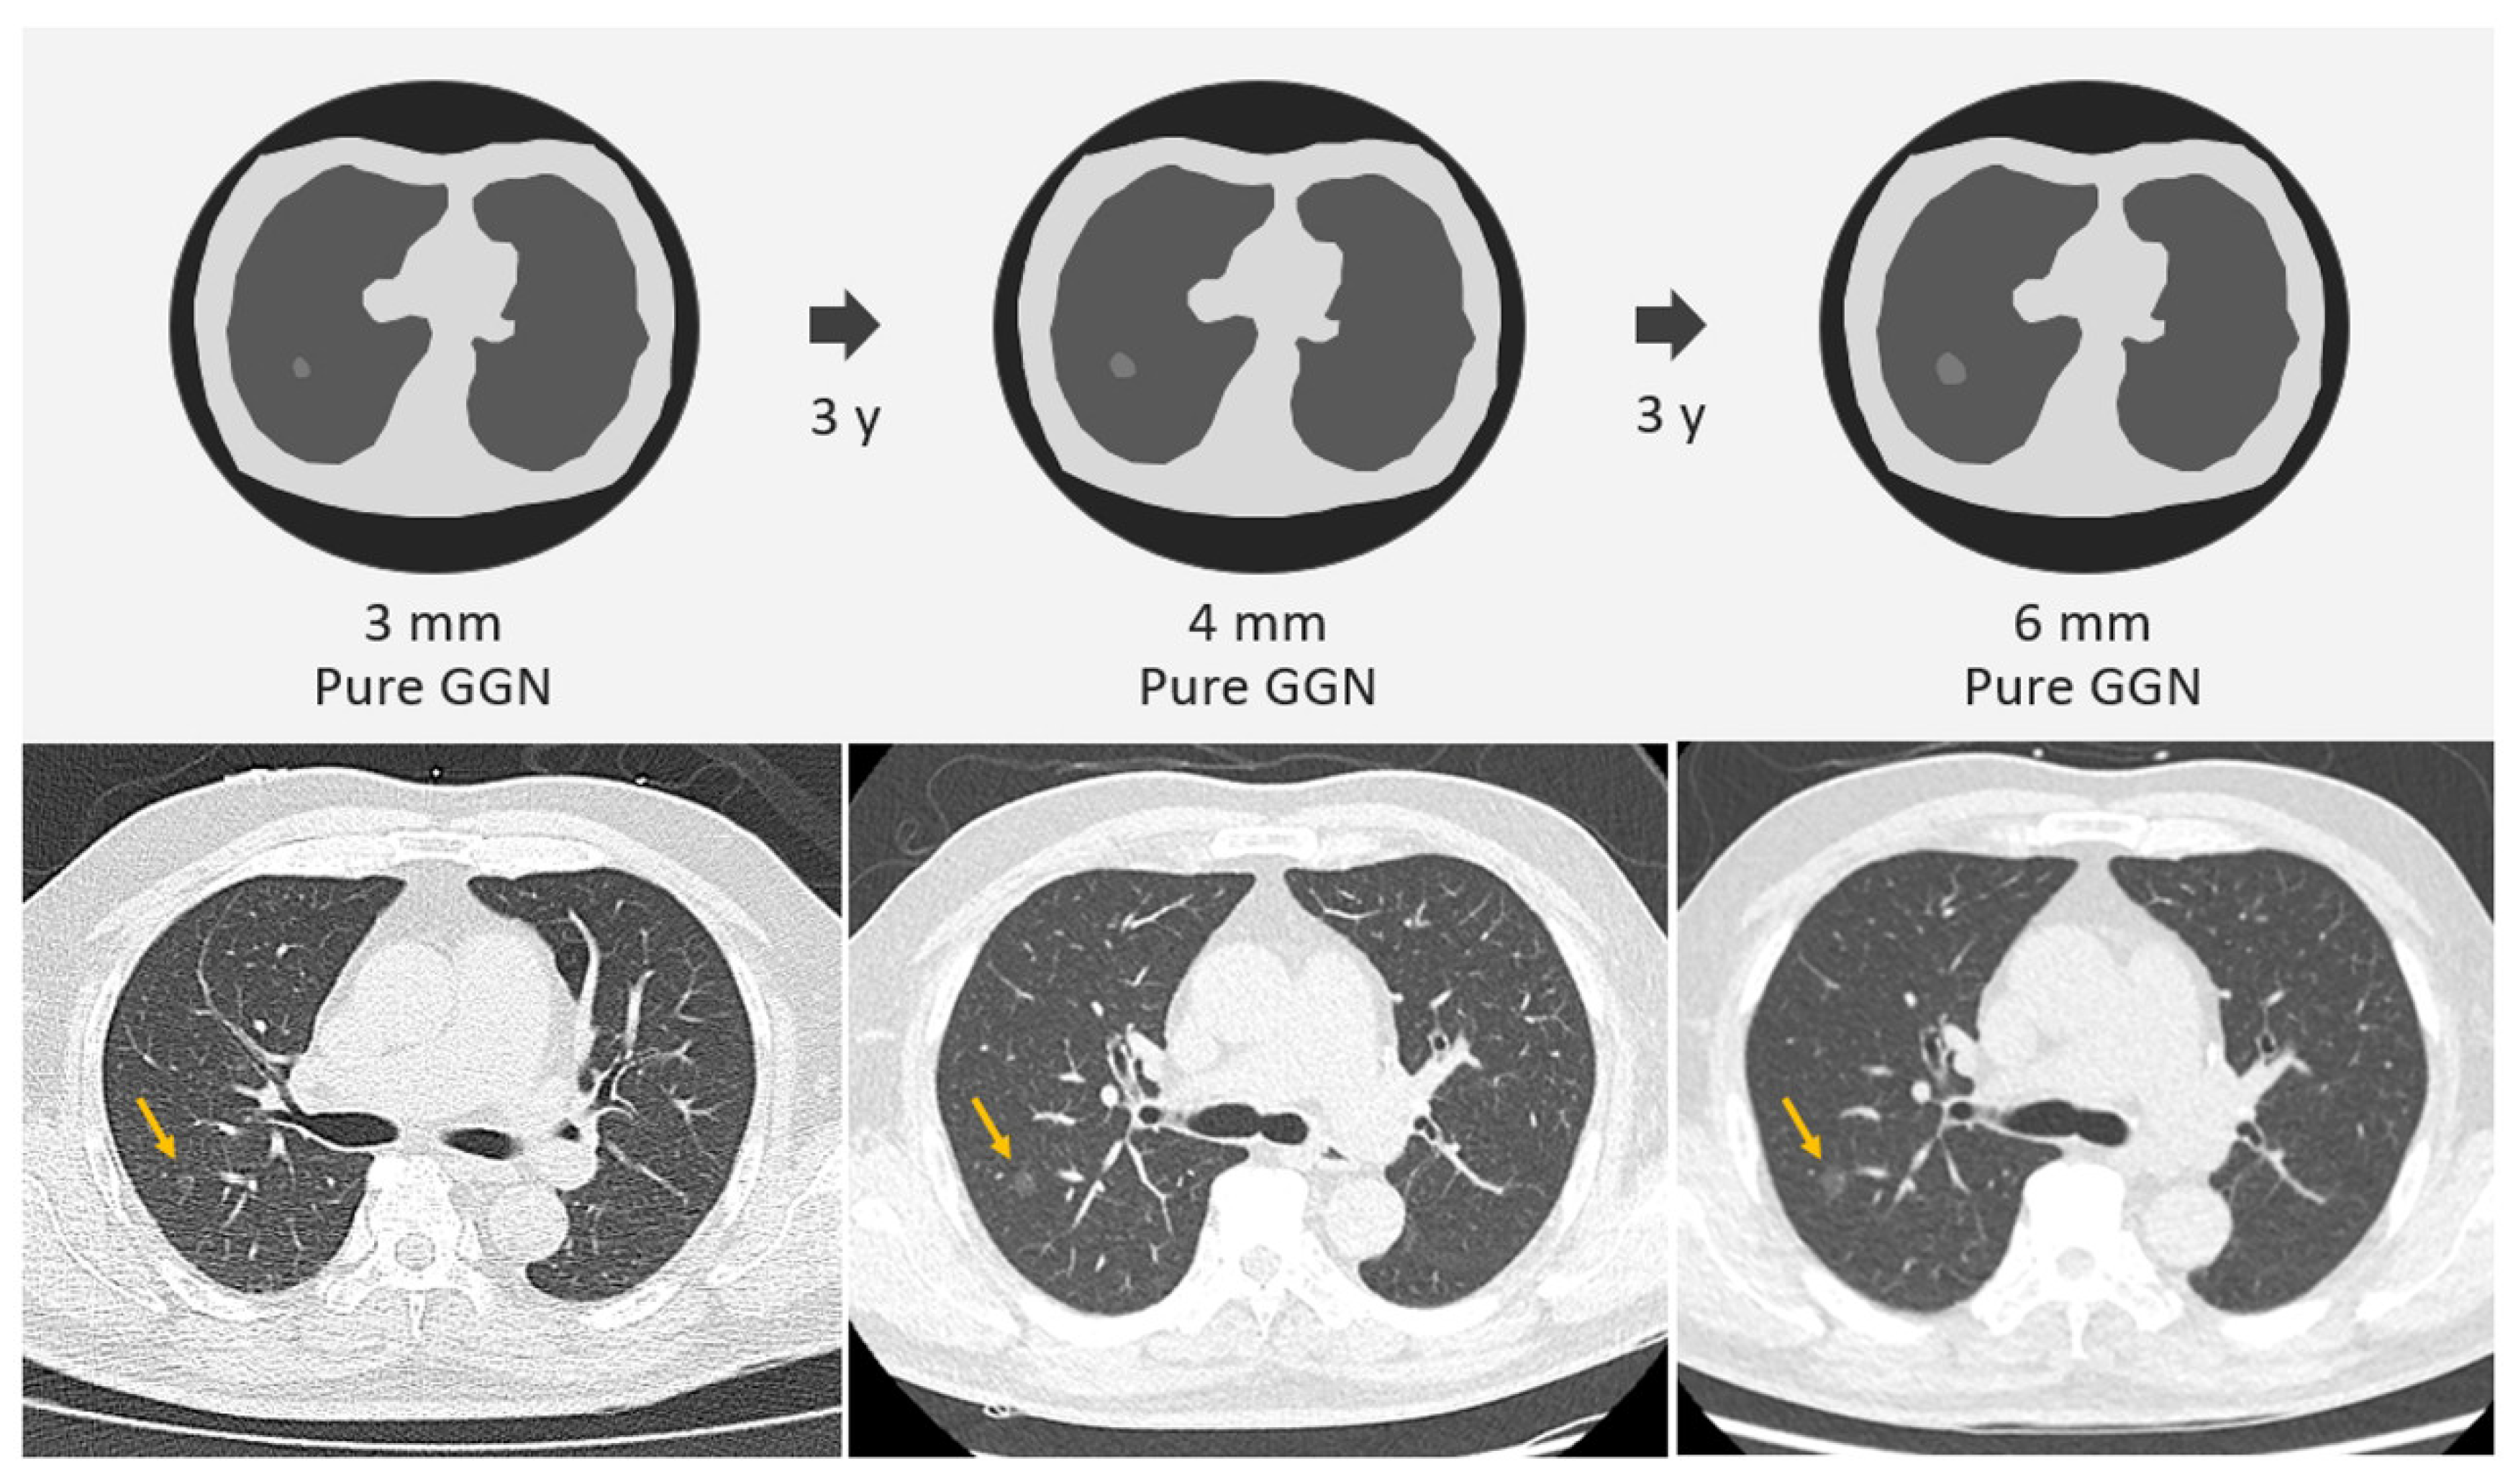

2.1. SSNs Interval Growth with an Increase of ≥2 mm

2.2. SSNs Interval Growth with an Increase of ≥5 mm